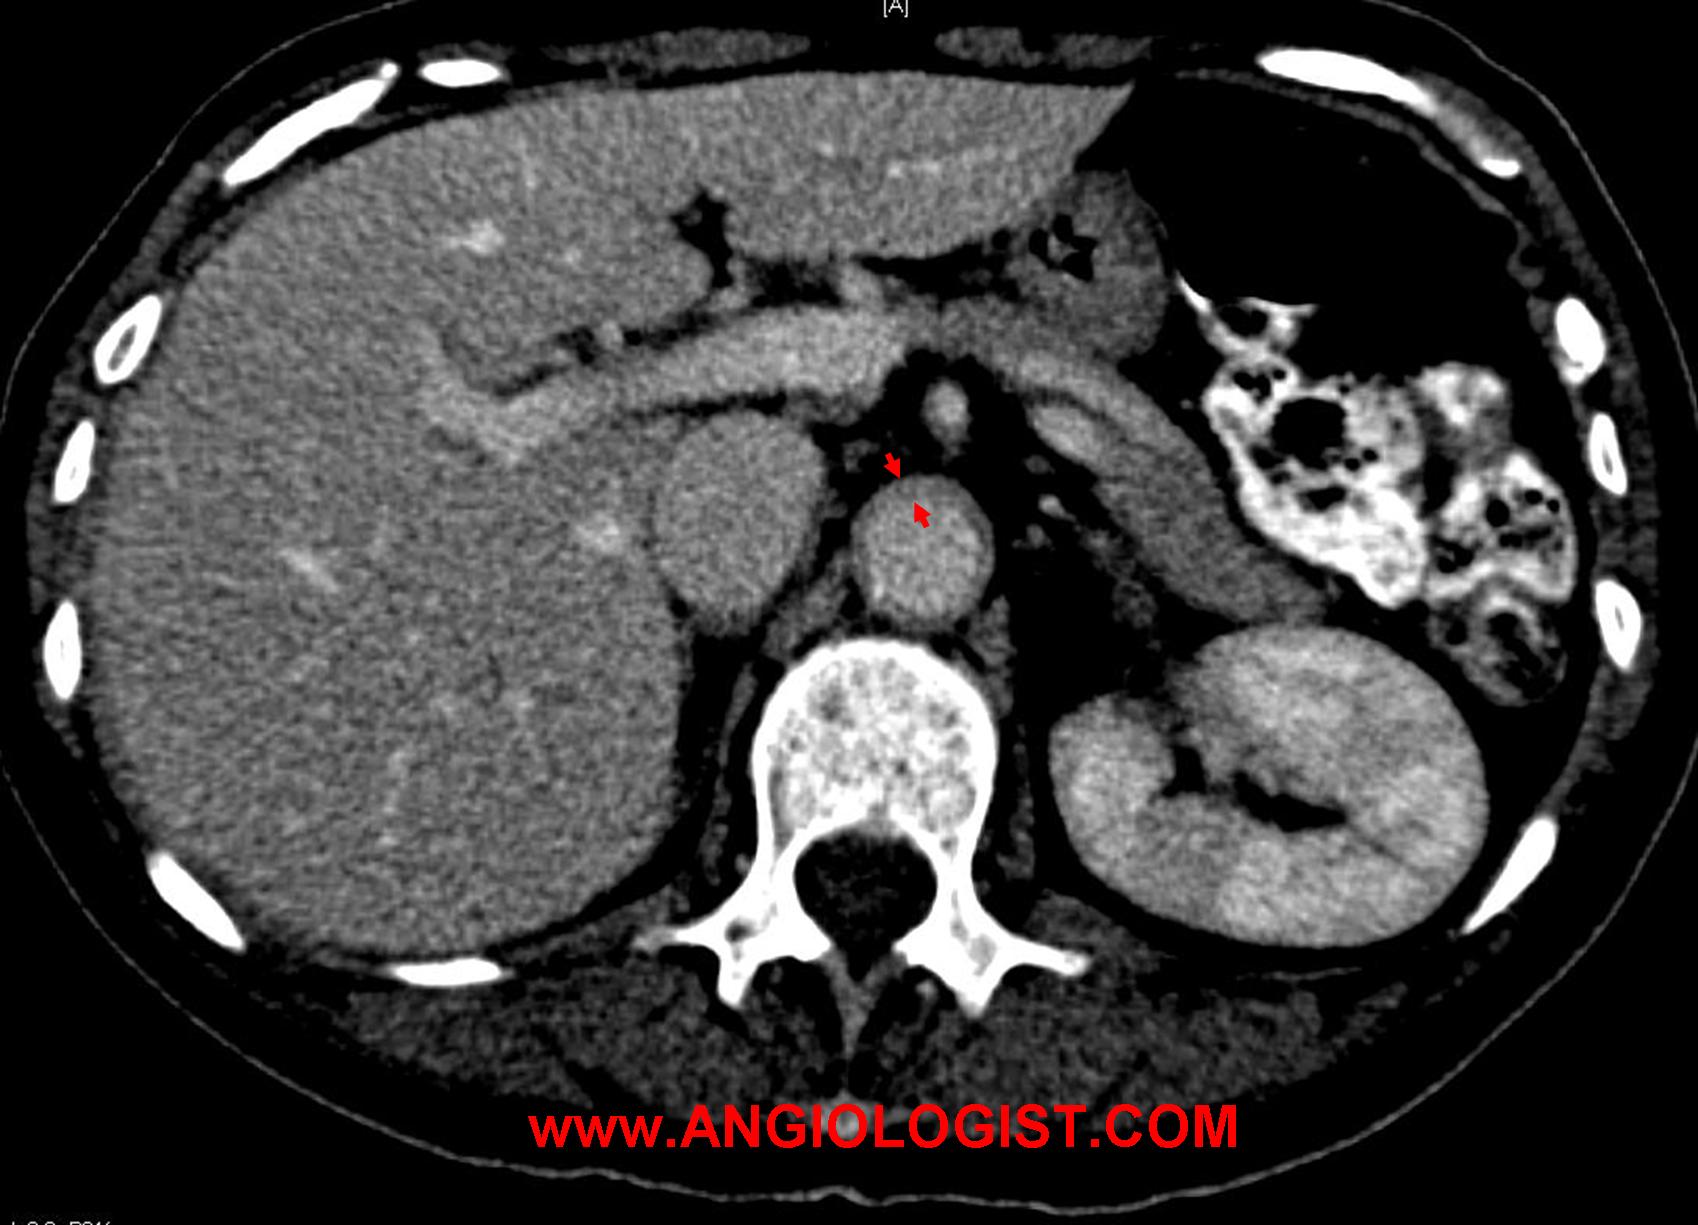

- Large artery involvement (aortic arch syndrome) alone or in conjunction with the other clinical manifestations of giant cell arteritis is typical. An aortic aneurysm can be diagnosed years after the disease has manifested. Still, it is not clear how to screen for aortic involvement, how often and for how long. Less commonly, other large arteries may be involved. For instance, the lower extremity arteries.

- Computed tomography – CT with contrast can be useful both for the diagnosis of arterial inflammation and for the diagnosis of possible vascular complications of giant cell arteritis.

As I wrote above, aneurysms can be a complication of the inflammatory process. Surgical resection of these aneurysms has been described with good overall results. The aneurysms may be a remnant of past disease or present during active phases. If the disease is active, surgery should be postponed, if possible, until the inflammation cools off. Anti-inflammatory medication is sometimes added after surgery The timing of this treatment after surgery is unclear, as early treatment may interfere with healing, while late treatment may expose patients to further complications.